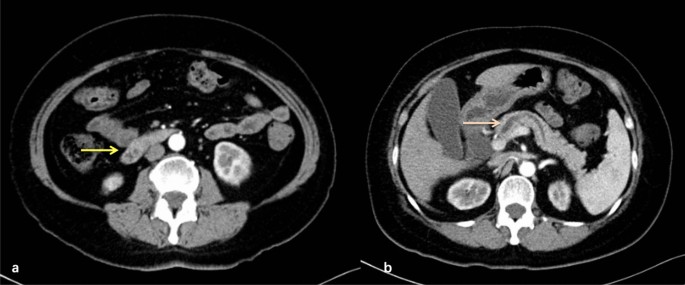

Contrast-enhanced abdominal computed tomography performed 6 months ago suggested dilatation of intra- and extrahepatic bile ducts and the pancreatic duct and the presence of suspicious nodules at the duodenal papilla (Fig. 3). Afterwards, she presented with yellow sclera and skin, choluria and clay colored stool that persisted for 3 months. Laboratory examinations revealed 64.6 μmol/L total bilirubin (normal, 5.1–22.2 μmol/L), 50.0 μmol/L direct bilirubin (normal, 0–6.8 μmol/L), elevated transaminase levels, including 38U/L alanine aminotransferase (normal, 7–40 U/L), 80U/L aspartate aminotransferase (normal, 13–35 U/L) and cholestasis parameters, including 1411U/L γ-glutamyl transpeptidase (normal, 7–45 U/L), 314U/L alkaline phosphatase (normal 50–135 U/L). Tumor markers carbohydrate antigen 19–9 was 58.1U/ml (normal, 0–34 U/ml)while levels of other tumor markers were within normal limits. Magnetic resonance cholangiopancreatography (MRCP) showed the common bile duct and main pancreatic duct were suddenly narrowed in the duodenal ampulla and the upstream bile duct was obviously dilated suggesting the presence of an ampullary tumor (Fig. 4a). Neither Lymph node enlargement nor distant metastasis were found. Endoscopic retrograde cholangiopancreatography (ERCP) showed a bulging protrusion at the ampulla of Vater which was diagnosed on biopsy to be poorly differentiated adenocarcinoma (Fig. 4b). Implantation of bile duct and pancreatic duct plastic stent was performed during ERCP. PET/CT showed an increased metabolic focus of 1.0 × 0.8 cm and SUVmax 4.0 at the duodenal papilla area considered to be malignant lesions, the properties of which still needs to be determined (Fig. 4c). The patient has lost 8 kg for the last 3 months.